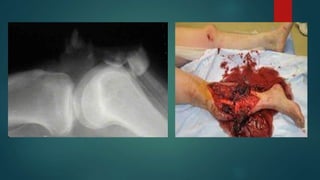

2. Compound fracture:

 Also known as open fracture

 Break in the overlying skin and soft tissues

 Communicating with the external environment

a. Internal compounding:

 Compounding from within

 Sharp fracture end pierces the skin from within

b. External compounding:

 Compounding from without

 Object causing the fracture lacerates the skin and soft tissues over the bone

ON THE BASISOF RELATIONSHIP WITH EXTENRAL ENVIRONMENT 1. Simple fracture:  Fracture not communicating with the external environment  Overlying skin and the other soft tissues are intact  Also known as closed fracture 2. Compound fracture:  Also known as open fracture  Break in the overlying skin and soft tissues  Communicating with the external environment

a. Internal compounding: Compounding from within  Sharp fracture end pierces the skin from within b. External compounding:  Compounding from without  Object causing the fracture lacerates the skin and soft tissues over the bone